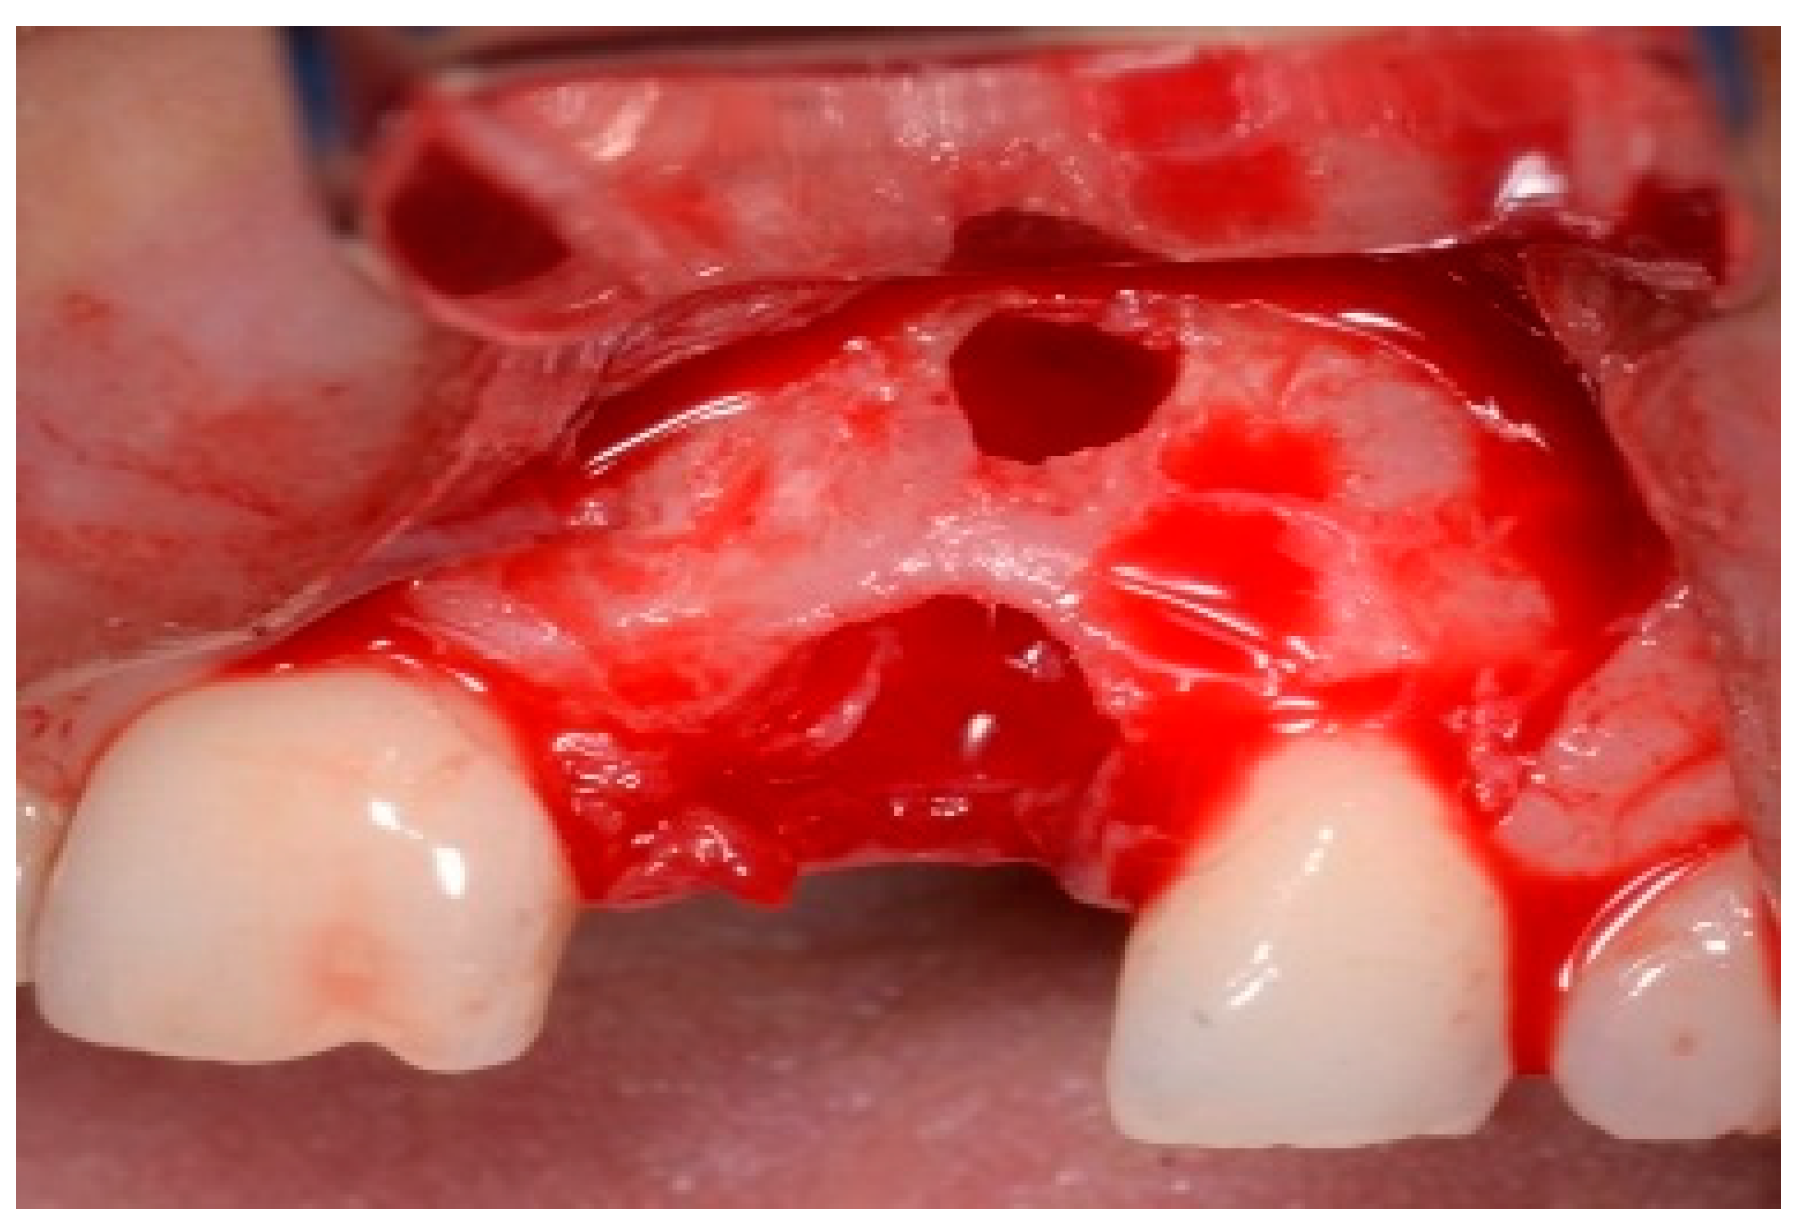

One hour before the surgical procedure, the patient received a prophylactic dose of 1 g of amoxicillin. Following local anesthesia, surgical access was obtained by raising a full-thickness aesthetic flap extending to the distal line angles of the lateral incisors. The full-thickness flap was extended 3–5 mm beyond the apical margin of the defect. The two central incisor roots were extracted, and the sockets were curetted with surgical curettes to remove all the granulation tissue (Figure 2). The sockets were assessed for the presence of a dehiscence and or fenestration. Two implants (Adin Dental Implants, Englewood, NJ, 07632, USA) were placed according to the manufacturer’s instructions (Figure 3).

Figure 2.

Clinical view immediately after extraction.